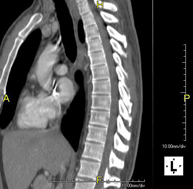

- TC Columna DorsalPrueba radiológica que consiste en obtener imágenes de las vértebras dorsales de alta definición anatómica mediante el empleo de un equipo de TC (Tomografía Computarizada). Indicaciones: dolor dorsal agudo/crónico, traumatismo, columna desviada.

- TC Columna dorsal Prova radiològica que consisteix en obtenir imatges de les vèrtebres dorsals d'alta definició anatòmica, mitjançant l'ús d'un equip de TC (Tomografia Computaritzada). Indicacions: dolor dorsal, estudi de desviacions de la columna, traumatisme. Prova radiològica que consisteix en obtenir imatges de les vèrtebres dorsals d'alta definició anatòmica, mitjançant l'ús d'un equip de TC (Tomografia Computaritzada). Indicacions: dolor dorsal, estudi de desviacions de la columna, traumatisme.

- TC Columna lumbar Prova radiològica que consisteix en obtenir imatges de les vèrtebres lumbars d'alta definició anatòmica, mitjançant l'ús d'un equip de TC (Tomografia Computaritzada). Indicacions: dolor lumbar sense / amb irradiació a les cames, dificultat per caminar, traumatisme. Prova radiològica que consisteix en obtenir imatges de les vèrtebres lumbars d'alta definició anatòmica, mitjançant l'ús d'un equip de TC (Tomografia Computaritzada). Indicacions: dolor lumbar sense / amb irradiació a les cames, dificultat per caminar, traumatisme.